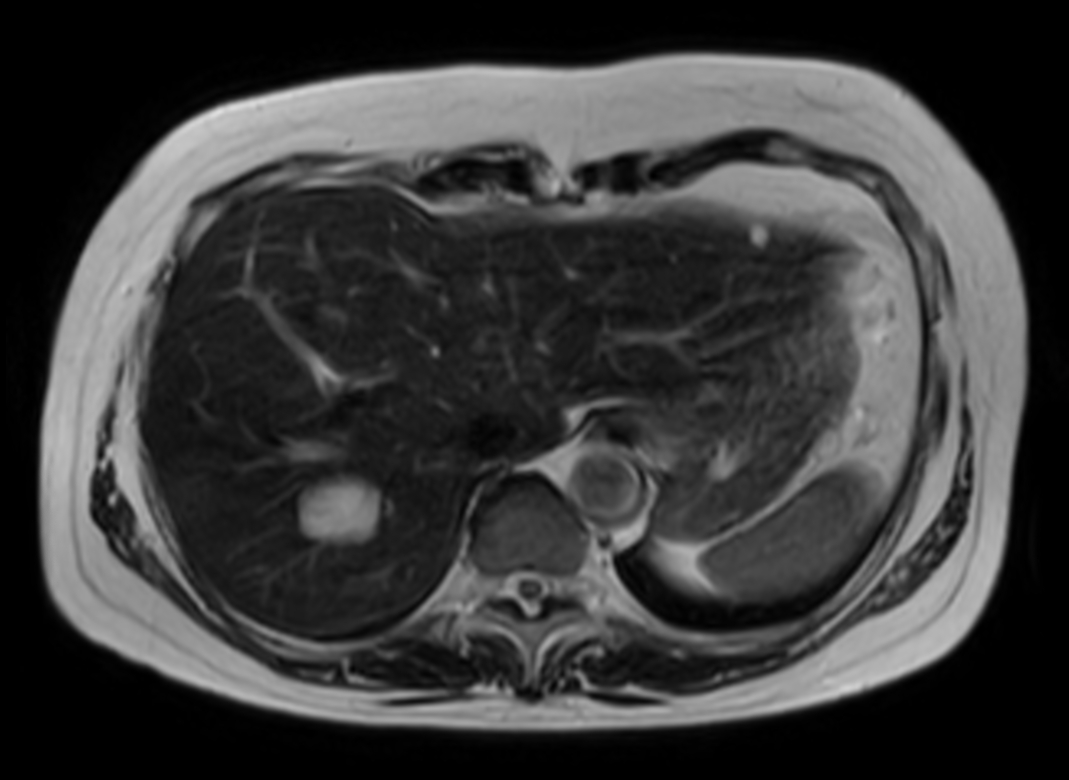

Axial T2w TSE (heavy)